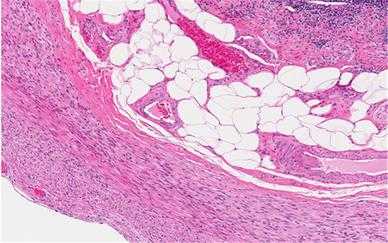

Помимо нескольких естественных пигментов, таких как меланин, клетки и другие элементы, составляющие большинство образцов бесцветные. Для того, чтобы выявить структурные детали с помощью светлопольной микроскопии, используются некоторые способы окрашивания. Окраска гематоксилином и эозином (H&E) повсеместно используется как отправная точка для предоставления важнейшей структурной информации. С помощью этого метода ядра клетки окрашиваются синим, а цитоплазма и многие дополнительные клеточные компоненты окрашиваются в оттенки розового. В гистопатологии многие состояния могут быть выявлены путем исследования только H&E.Однако иногда требуется дополнительная информация для того, чтобы обеспечить полную дифференциальную диагностику, а это требует дальнейшего, более специализированного метода окрашивания. Это могут быть «специальные пятна», сделанные с помощью красителей или металлических вкраплений для определения конкретной структуры микроорганизмов, или это могут быть иммунно-гистохимические методы, охватывающие расположение диагностически полезных белков с помощью отмеченных антител. Молекулярные методы, такие как гибридизация in-situ (ISH), также могут быть необходимыми для выявления специфических последовательностей ДНК или РНК. Все эти методы могут быть применены на парафиновых срезах, и в большинстве случаев полученные срезы полностью стабильны и могут храниться в течение многих лет.

Рис. 12. Окраска гематоксилином и эозином. Это микроскопическое изображение (микрофотография) парафинового среза стенки человеческого аппендикса, полученное с помощью светлопольной микроскопии. Клетки окрашены синим цветом, а гладкие мышцы, коллаген и другие компоненты открашены в оттенки розового. Большие пустые пространства относятся к жировым клеткам, жиры были растворены во время обработки.